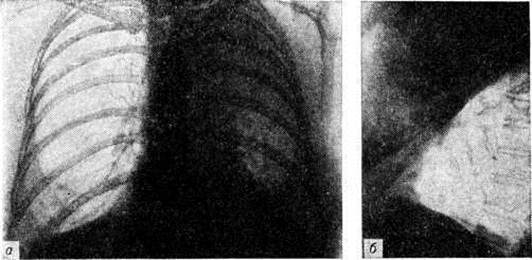

При перкуссии часто определяют признаки острого вздутия лёгких: тимпанит, низкое расположение краёв лёгких, уменьшение абсолютной сердечной тупости. Определяют небольшое укорочение перкуторного звука соответственно зоне инфильтрации и расширение корня лёгкого на поражённой стороне. При аускультации дыхание жёсткое, выслушиваются нестойкие скудные сухие хрипы, иногда сухих и влажных хрипов много. В некоторых случаях перкуторные и аускультативные признаки выражены слабо или отсутствуют. Часто между клинические, и рентгенологическое признаками гриппозных Пневмония наблюдается расхождение. Так, при выраженных рентгенологическое признаках пневмонической инфильтрации отсутствуют её физикальные проявления или, напротив, у больных с клинически выраженными признаками Пневмония рентгеноскопически и рентгенографически определяют лишь небольшое расширение прикорневых теней и отставание экскурсий диафрагмы. По данным Н. С. Молчанова (1971), чаще других поражаются задние сегменты верхних долей, верхушечный и задний базальный сегменты нижних долей. В начале заболевания выражена тахикардия, АД несколько повышается в первые дни болезни, а затем снижается.

При очаговой Пневмония умеренный лейкоцитоз отмечается лишь у половины больных. Более характерны нейтрофильный сдвиг влево, ускоренная РОЭ, уменьшение или исчезновение эозинофилов. При выраженных явлениях интоксикации может наблюдаться протеинурия, микрогематурия и цилиндрурия. У больных с очаговой Пневмония снижены жизненная ёмкость лёгких и максимальная вентиляция, повышены минутный объем дыхания, отношение остаточного объёма к общей ёмкости лёгких. У 23% больных отсутствуют убедительные клинические, признаки очаговой Пневмония, и диагноз ставят на основании рентгенологическое данных.